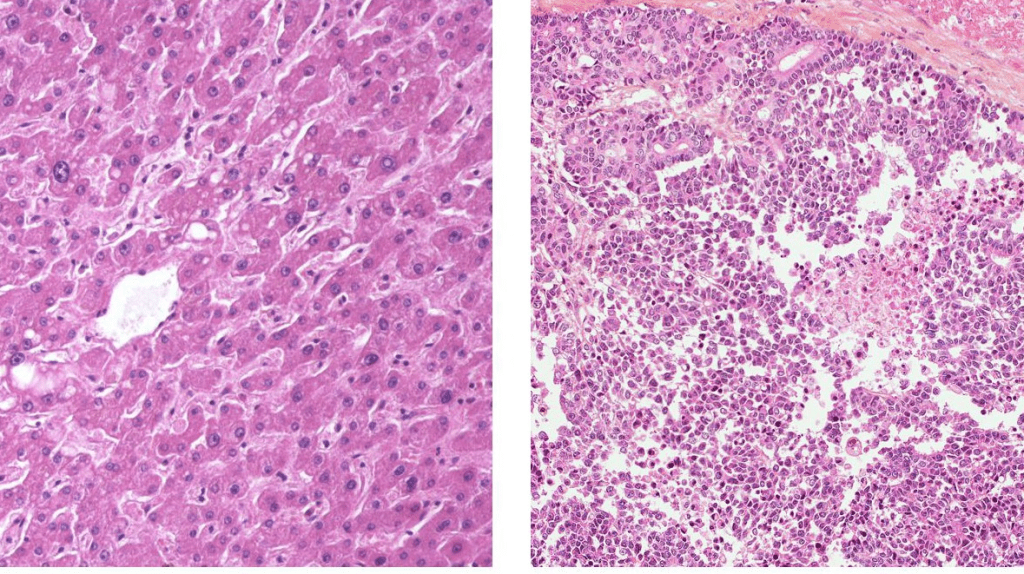

Tumor Biology and Genetic Markers

The type of tumor is a big factor in hepatoblastoma prognosis. Genetic markers and the tumor’s look really matter. Some genetic changes can make the tumor grow faster or respond better to treatment. High levels of alpha-fetoprotein (AFP) at first can mean a tougher disease. But, if AFP goes down while treating, it’s a good sign.